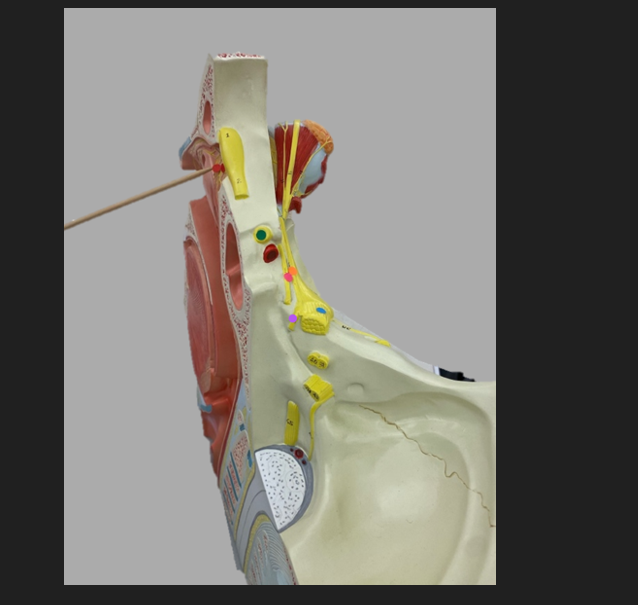

green dot

spinal nerve

orange dot

ventral root

pink dot

dorsal root

blue dot

dorsal root ganglion

red dot

dorsal ramus

yellow dot

ventral ramus

purple dot

anterior median fissure

red dot

posterior (dorsal) horn

purple dot

lateral horn

dark blue dot

anterior (ventral) horn

orange dot

dorsal column

yellow dot

lateral column

dark green

anterior column

line green and pink doit

gray commissure

light blue dot

posterior median sulcus